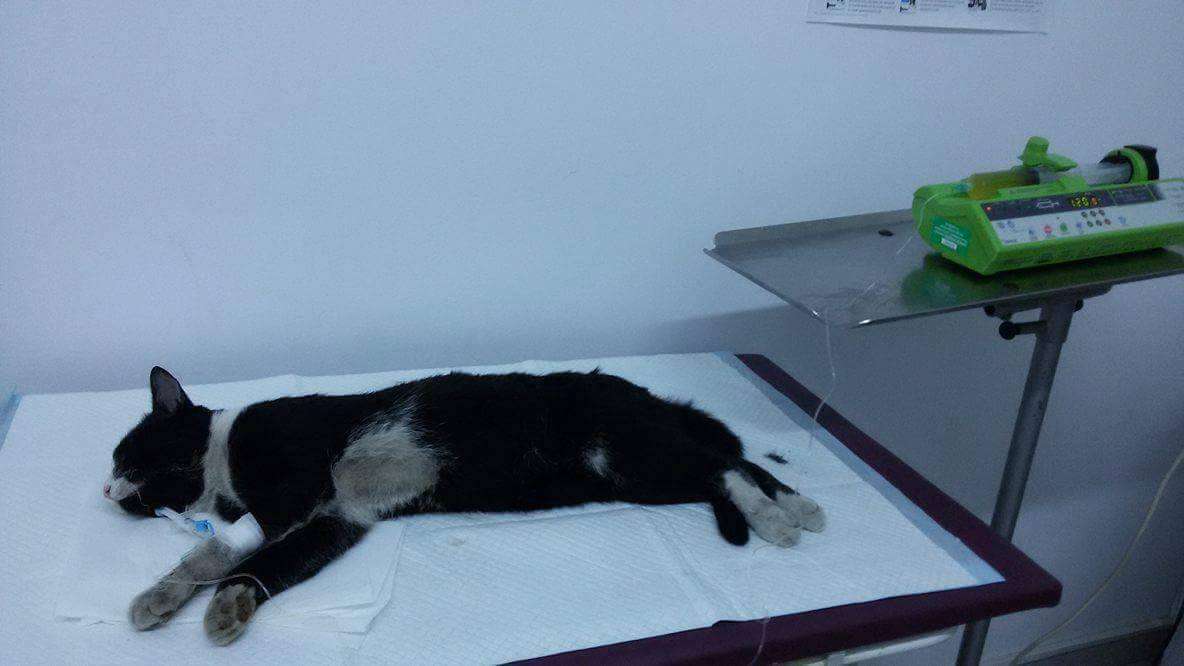

He was lying in the road, with a fractured mandible>

We shall probably never know whether he was beaten and abandoned, or he was thrown out and then beaten by someone, or perhaps suffered an accident. What is certain is that he had 3 fractures of the mandible and one of his jaw, so that he had all the chances to a slow and tortured death. However, a star was shining in the sky for him, since a good man was lead to find him and take him to the clinic, where he underwent surgery. He is now at the APAM Sanctuary, while still having the wires that support his jaw. He has begun to eat soft food, and we hope he will soon be all healed, and then we can find him a family to love him and give him the assurance that he would never be abandoned again.

He was lying in the road, with a fractured mandible